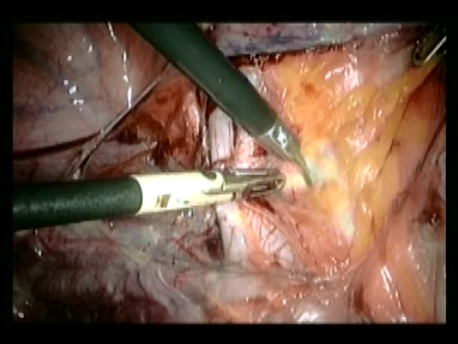

Endometrial cancer is cancer of the lining of the uterus. The treatment of early stage endometrial cancer is a simple hysterectomy and, in select cases, pelvic lymphadenectomy (specialized organs which drain tissue fluid). Laparoscopic surgery is the route of choice for treatment of endometrial cancer.